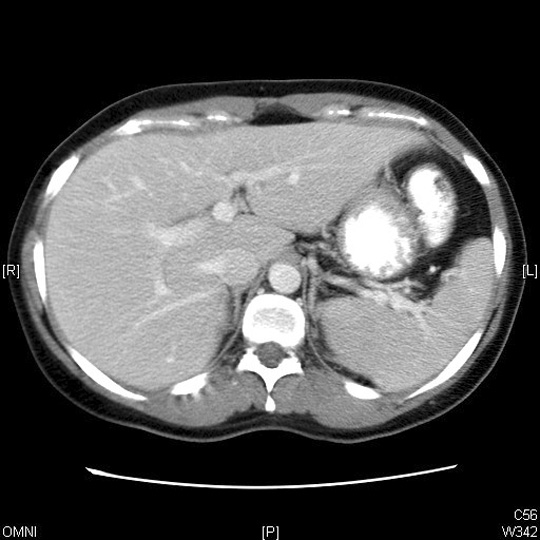

Identify the structures around the diaphragmatic crus. Click the image for labeling.